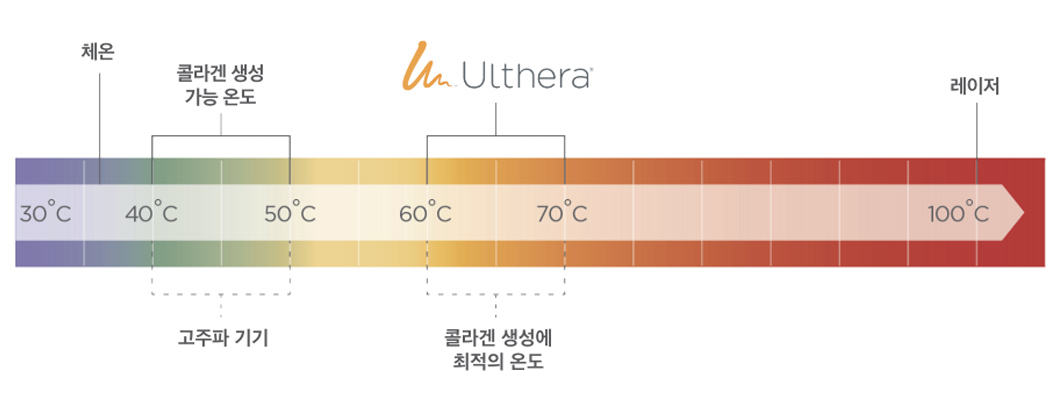

울쎄라피 프라임은 새로운 콜라겐 생성 및 재생을 위한

최적의 온도인 60~70도의 열을 표적조직에 정확하게 전달합니다.